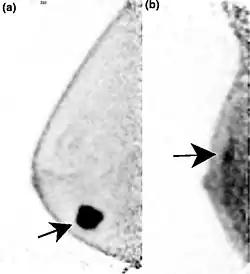

Two PEM images, including sites of tracer uptake